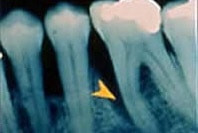

Im Frühstadium ist Parodontitis schmerzlos und lässt sich so am besten behandeln. Deshalb ist eine regelmäßige zahnärztliche Kontrolle wichtig. Bei der zahnärztlichen Untersuchung misst der Zahnarzt die Taschentiefen. Zusätzlich können Röntgenaufnahmen dabei helfen, einen möglichen Knochenabbau sichtbar zu machen. Die häufigsten Symptome sind bei voranschreitender Gingivitis:

Bei länger bestehender Gingivitis greift die Entzündung vom Zahnfleisch auf den die Zahnwurzel stützenden Kieferknochen über und beginnt diesen abzubauen. Es bilden sich zunächst Zahnfleisch-, dann Knochentaschen, in deren Tiefe zahnsteinartige Ablagerungen den Entzündungsprozess weiter verstärken können.

Fortgeschrittene Parodontitis mit tiefer Knochentasche